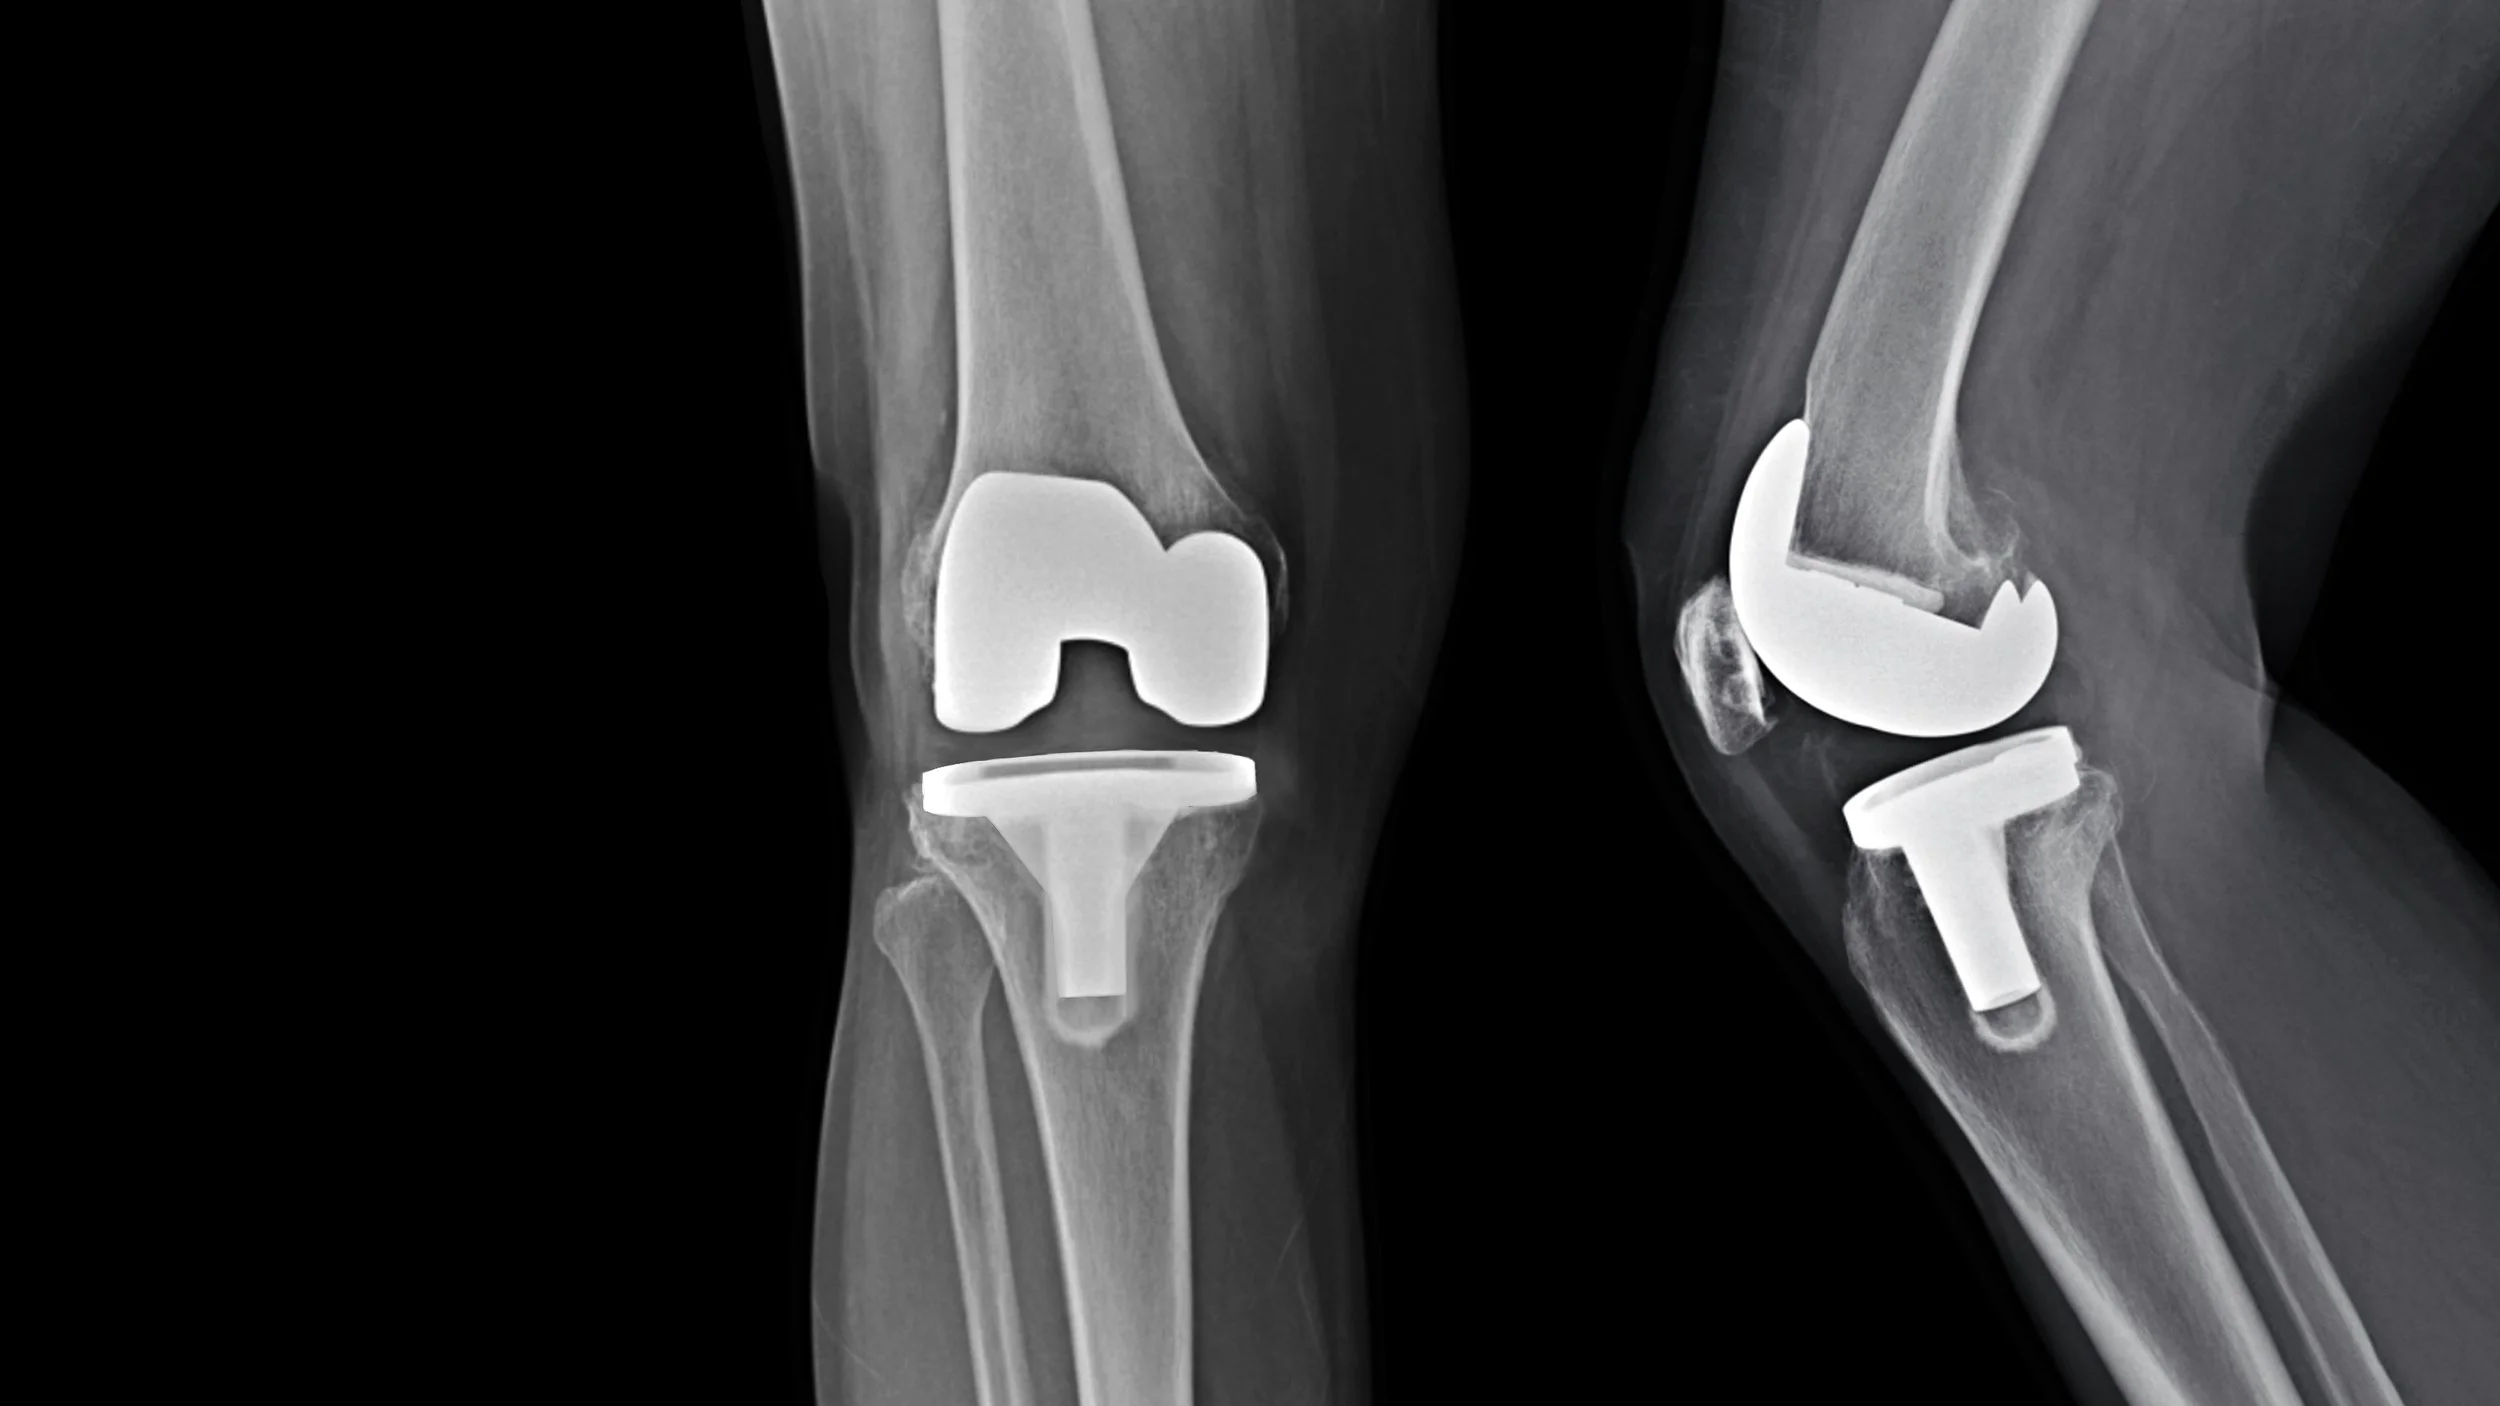

Knee Replacement

Total knee replacement (TKR) surgery is a common procedure for severe knee arthritis or joint damage. Post-surgery, physiotherapy plays a crucial role in regaining knee movement, rebuilding strength, and improving functional ability. Early and consistent rehabilitation can help you recover faster, prevent complications, and maximise the long-term success of your new knee joint.

Physiotherapy for total knee replacement focuses on restoring knee mobility, improving strength, reducing pain, and helping you regain independence and return to daily activities or sport safely